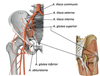

- Rotatorcuffen – m. supraspinatus, m. infraspinatus, m. terese minor och m. subscapularis

Vilken funktion har rotatorcuffen?

- Funktion, hålla humerus på plats på scapula

- Oavsett hur armen rörs ska ledkulan ligga centrerat i ledpannan (mot glenoiden) och detta är rotatorcuffens funktion

Vilka starka muskler jobbar i axelleden? Och varför är dessa muskler starkare än andra?

- M. pectoralis major

- M. deltoideus (mkt stark)

- Ventral del flekterar, lateral abducerar och posterior som extenderar

- M. latisimus dorsi

Starka muskler fäster lite längre ifrån rotationscentrum, vilket medför att de genererar mer kraft